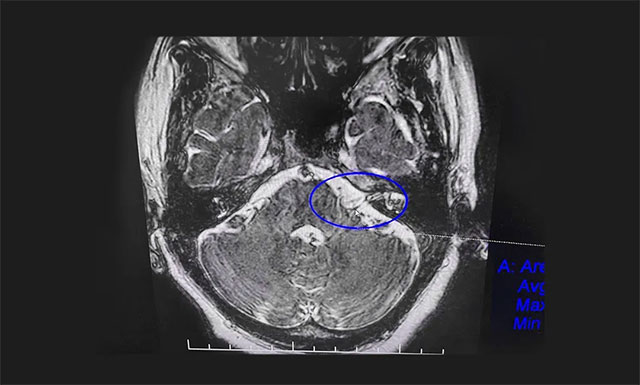

▲ 患者左侧面神经根与小血管关系密切

患者范阿姨入院后,面神经MRTA平扫+增强检查显示,患者左侧面神经颅内段根部与周围小血管关系密切。沈建康教授团队对患者病情及影像学资料进行充分评估后认为,患者药物治疗效果不佳,症状反复发作,已影响日常生活,有手术指征,未见明显手术禁忌症。在告知患者及家属手术风险后,沈教授团队为患者开展了面神经微血管减压手术。